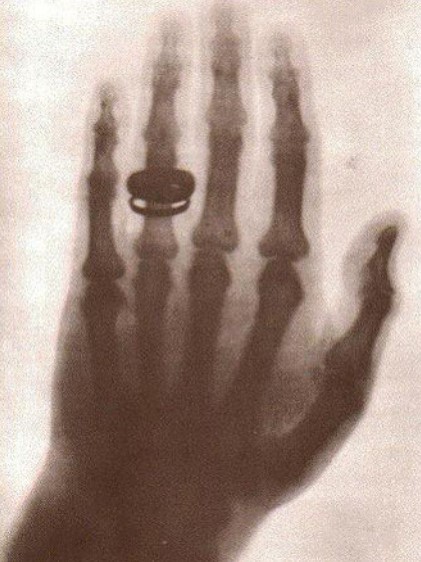

뢴트겐은 재미있는 실험을 생각해 내었습니다. 바로 사진을 찍을 때 사용하는 사진 건판에 이 광선을 통과시켜 보는 것이었습니다. 사진 건판에 빛이 닿으면 하얗게 변하는 것을 아내에게 자랑하고 싶은 마음에 아내의 손을 건판에 올려놓고 광선을 통과시켰습니다. 잠시 후 놀라운 일이 벌어졌습니다. 광선이 닿은 사진 건판이 하얗게 변하면서 그 위에 부인의 손 뼈 모양이 그대로 찍힌 것입니다. 결혼반지도 함께 말입니다. 부인도 깜짝 놀라 소리쳤습니다. 뢴트겐은 아내의 손 뼈 사진을 찍음으로써 자신이 발견한 이 정체 모를 광선에 대해 확신을 가지게 되었습니다. 그래서 이 광선에 대한 본격적인 연구를 시작했고 얼마 후 한 편의 멋진 논문을 완성하였습니다. 하지만 한 가지 고민이 남아 있었습니다. 자신이 발견한 이 광선을 부를 만한 이름이 없었던 것입니다. 지금까지 알려지지도 않았고 아직 정확히 알 수 없었기 때문에 엑스선이라고 부르기로 했습니다. 1895년 12월 자신의 논물을 학회에 발표하고 엑스선을 인정받게 되었습니다.